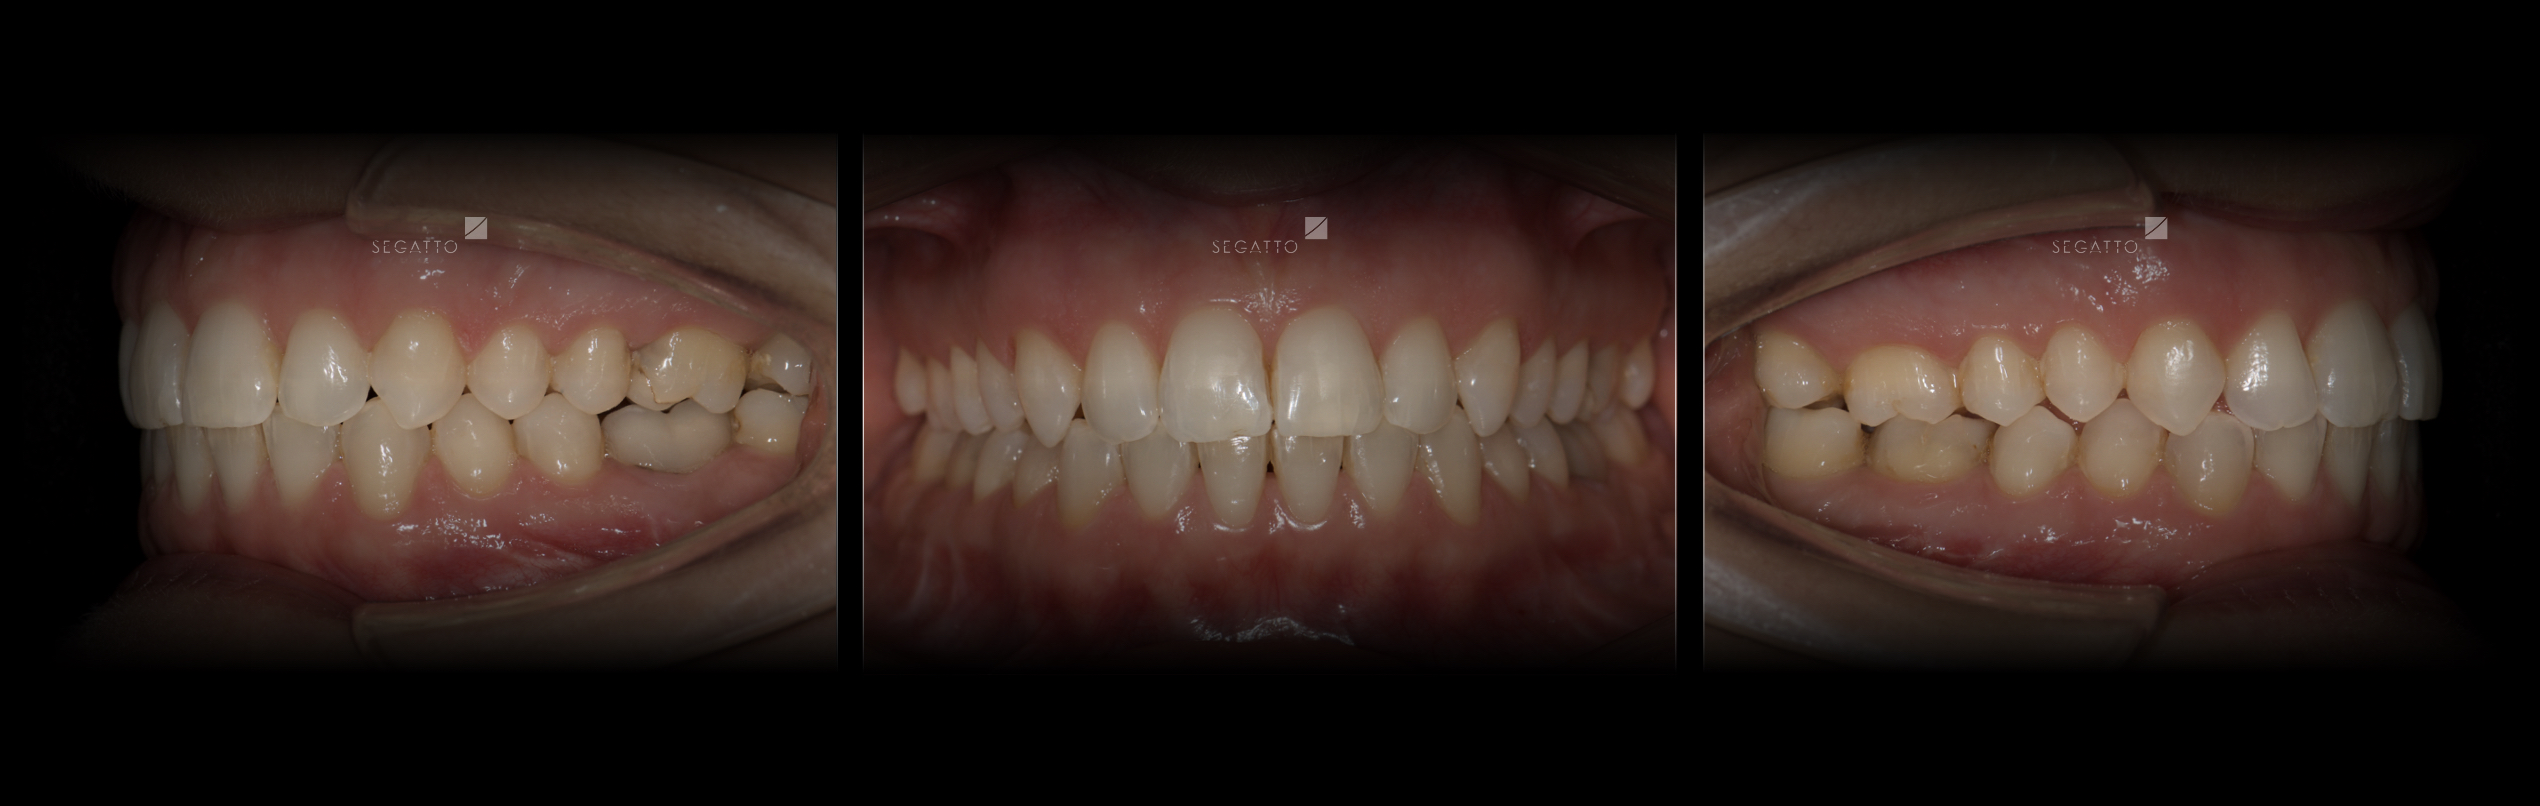

Orthodontics

Cases